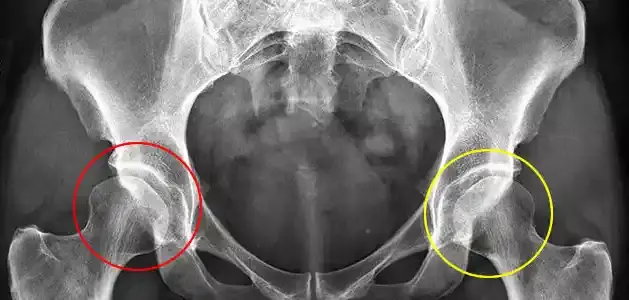

- الأشعة فوق الصوتية التي تُظهر تفاصيل المفصل الغضروفي الذي لا يظهر بالأشعة العادية بعد.

- الأشعة السينية عندما يبدأ العظم بالتكوّن بشكل أوضح.